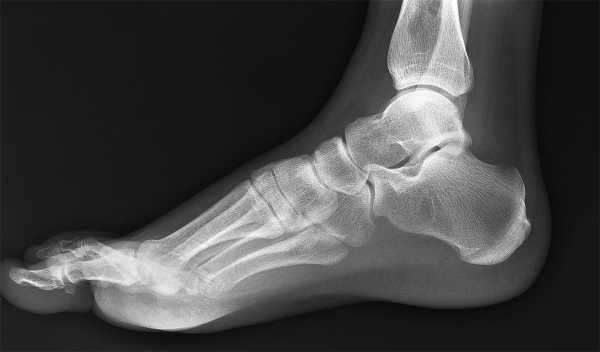

Для того чтобы различить степень деформации стопы и выявить группу здоровья призывника, необходимо произвести рентгеновский снимок свода стопы, а также осмотр хирурга. Заключение может выдвинуть только хирург-ортопед. Для постановки диагноза необходимо описание рентгеновского снимка, который делается в вертикальном положении. Так заметнее нагрузка на стопу. В описании уточняется угол наклона стопы и угол Белера, который описывает степень деформации пяточной кости в стопе.

Для более точного диагноза, при тяжелой степени плоскостопия, рекомендуется пройти компьютерную томографию, которая поможет оценить нормальное развитие и функционирование подтаранного сустава.

Сделанный рентген стопы покажет патологические изменения. При продольном плоскостопии:

1 степень — угол свода составляет 131 — 140 градусов, высота свода равна 25 — 35 мм. Деформация костей стопы отсутствует.

2 степень — угол свода составляет 141 — 155 градусов, высота свода равна 24 -17 мм. На рентгеновском снимке можно увидеть следующие изменения: таранная косточка становится короче, шейка не выражена. На тыльной поверхности стопы в месте, где располагается связочный аппарат, имеются изменения, характерные для деформирующего артроза. Патологии могут быть и в области таранно-ладьевидного сочленения.

3 степень — угол свода составляет 156 градусов или больше, а высота свода ниже 17 см. Выступ на поверхности кости пятки сильно увеличивается. Поперечный свод становится плоским. Пятка отклоняется.

При поперечном плоскостопии, которое мы знаем по росту «косточек» на больших пальцах, наблюдаются следующие изменения:

- 1 степень — угол между плюсневыми костями: 1 и 2 составляет 10 -12 градусов.

- 2 степень — угол между плюсневыми костями: 1 и 2 составляет 13 -15 градусов.

- 3 степень — угол между плюсневыми костями: 1 и 2 составляет 16 -20 градусов.

- 4 степень — угол между плюсневыми костями: 1 и 2 составляет более 20 градусов.

- Рентгенограмма. Диагностическую процедуру проводят в положении стоя, когда стопа под нагрузкой. После получения снимка рентгенолог составляет его описание — это основная информация, на основе которой врач может определить, годен человек или нет. В описании указывается угол и высота продольного свода.

- Определение угла Белера. Этот показатель указывает на степень деформации пяточной кости.

- Компьютерная томография. Исследование проводится в коронарной плоскости. В результате удается изучить состояние подтаранного сустава.